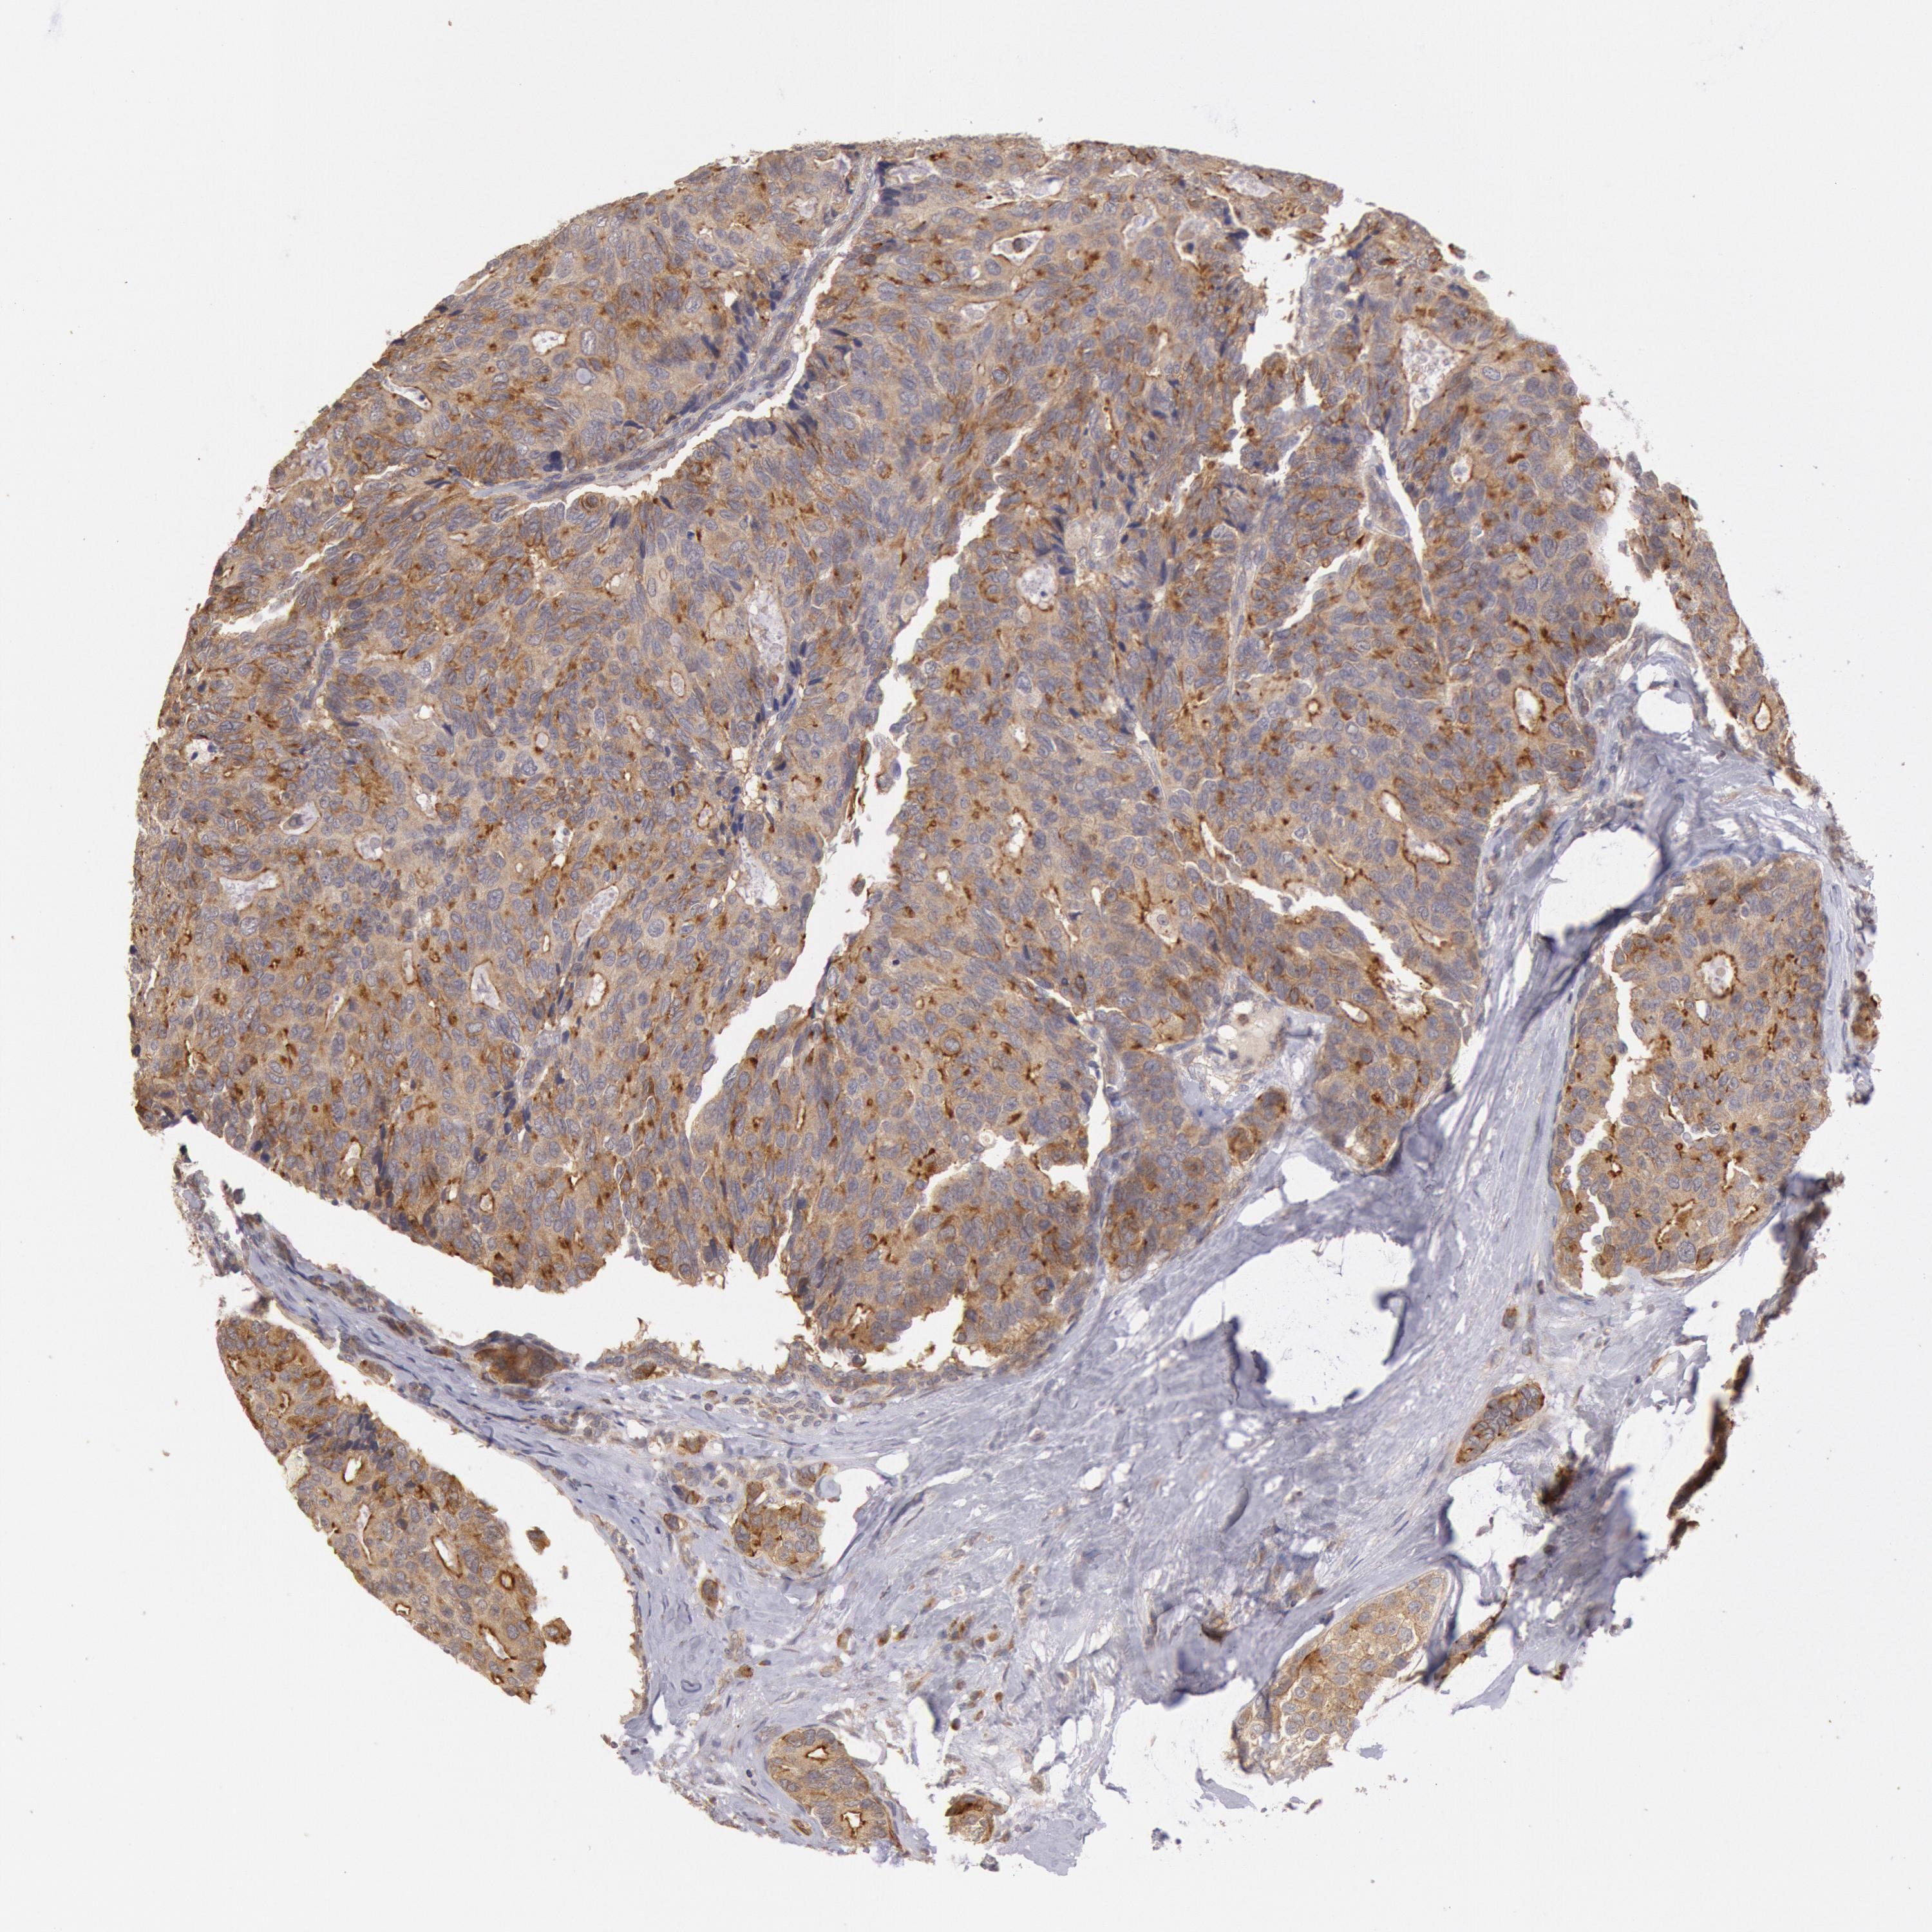

BRCA TCGA BRCA VALIDATION PROTEIN EXPRESSION